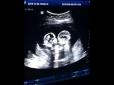

Хіти тижня. У мережі показали захоплююче відео бійки близнюків в утробі матері

Батько близнюків, 28-річний Тао, сказав, що дане відео було знято, коли він супроводжував свою дружину на допологовому огляді в кінці минулого року в китайському місті Іньчуань. Бійка близнюків сталася між сестрами-близнюками в утробі матері під час ул...